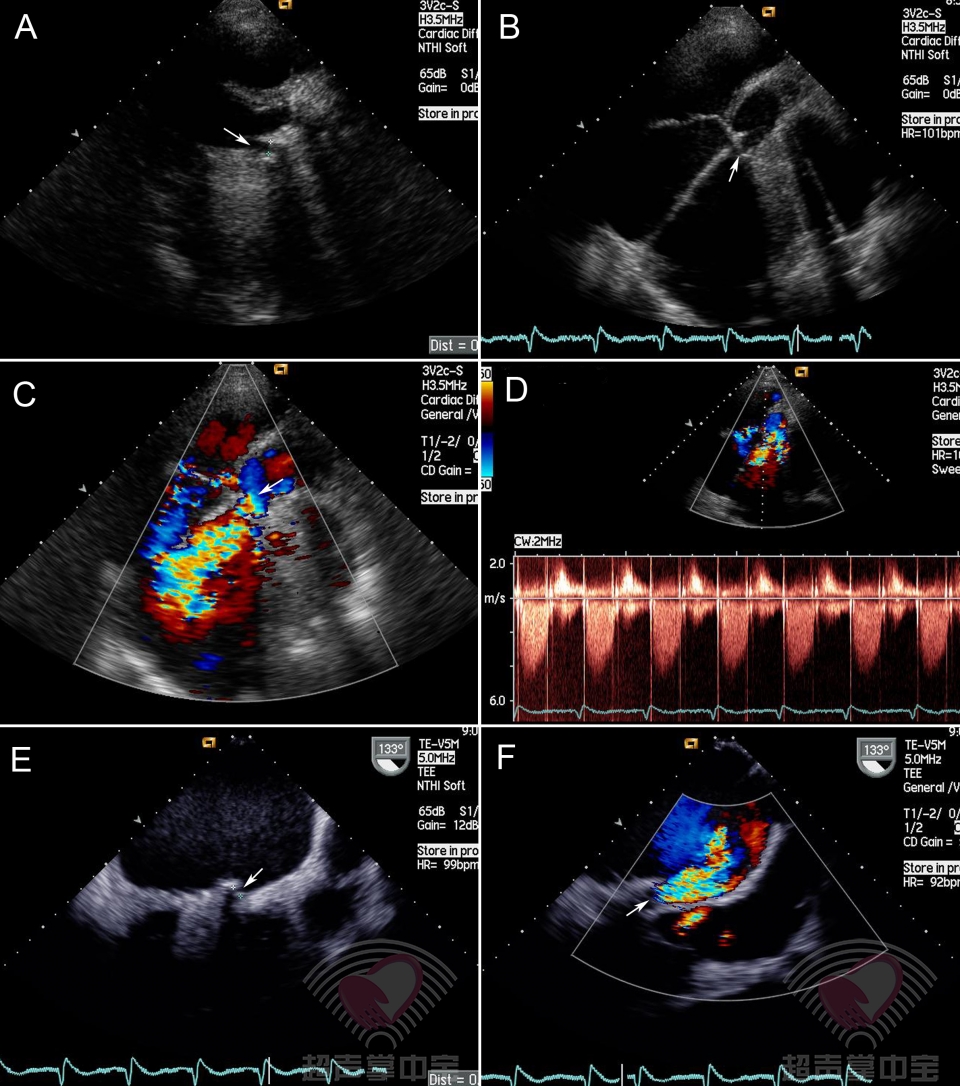

人工心脏瓣膜真实图片,二尖瓣机械瓣膜图片

二尖瓣机械瓣膜图片

心脏瓣膜图片超清

机械心脏瓣膜真实图片

心脏瓣膜真实图片

心脏瓣膜机械瓣膜图片

心脏瓣膜图片结构图

心脏瓣膜手术图片

心脏瓣膜图片